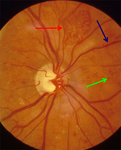

Proliferative diabetic retinopathy: new vessels on the optic disc (red circle), retrohyaloid haemorrhage (red arrow), new vessels elsewhere with fibrosis (white arrow), dot and blot haemorrhage (green arrow)

Courtesy of Moorfields Photographic Archive; used with permission